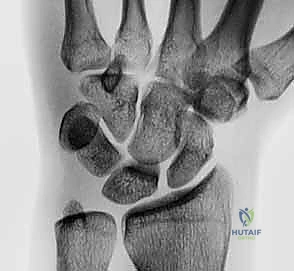

- Plain Radiographs: Often normal in dynamic LT instability. Clenched-fist anteroposterior, radial, and ulnar deviation views are essential. Look for disruption of Gilula arcs I and II, proximal translation of the triquetrum, or LT overlap, though a static LT gap is less common than in scapholunate injuries.

FIG 1 • A. Intact dorsal ligaments and normal carpal alignment. Loss of integrity of these secondary restraint structures, the volar-flexed position of the lunate, and the resulting volar intercalated segment instability (VISI) carpal collapse. B. Normal anatomic alignment of the carpus as viewed from a lateral radiograph. The lunotriquetral angle is 14 degrees. C. VISI carpal collapse visible on lateral radiograph. The lunate is volar-flexed and the lunotriquetral angle is 16 degrees. D. Rupture of the lunotriquetral interosseous ligament and the dorsal secondary restraint.